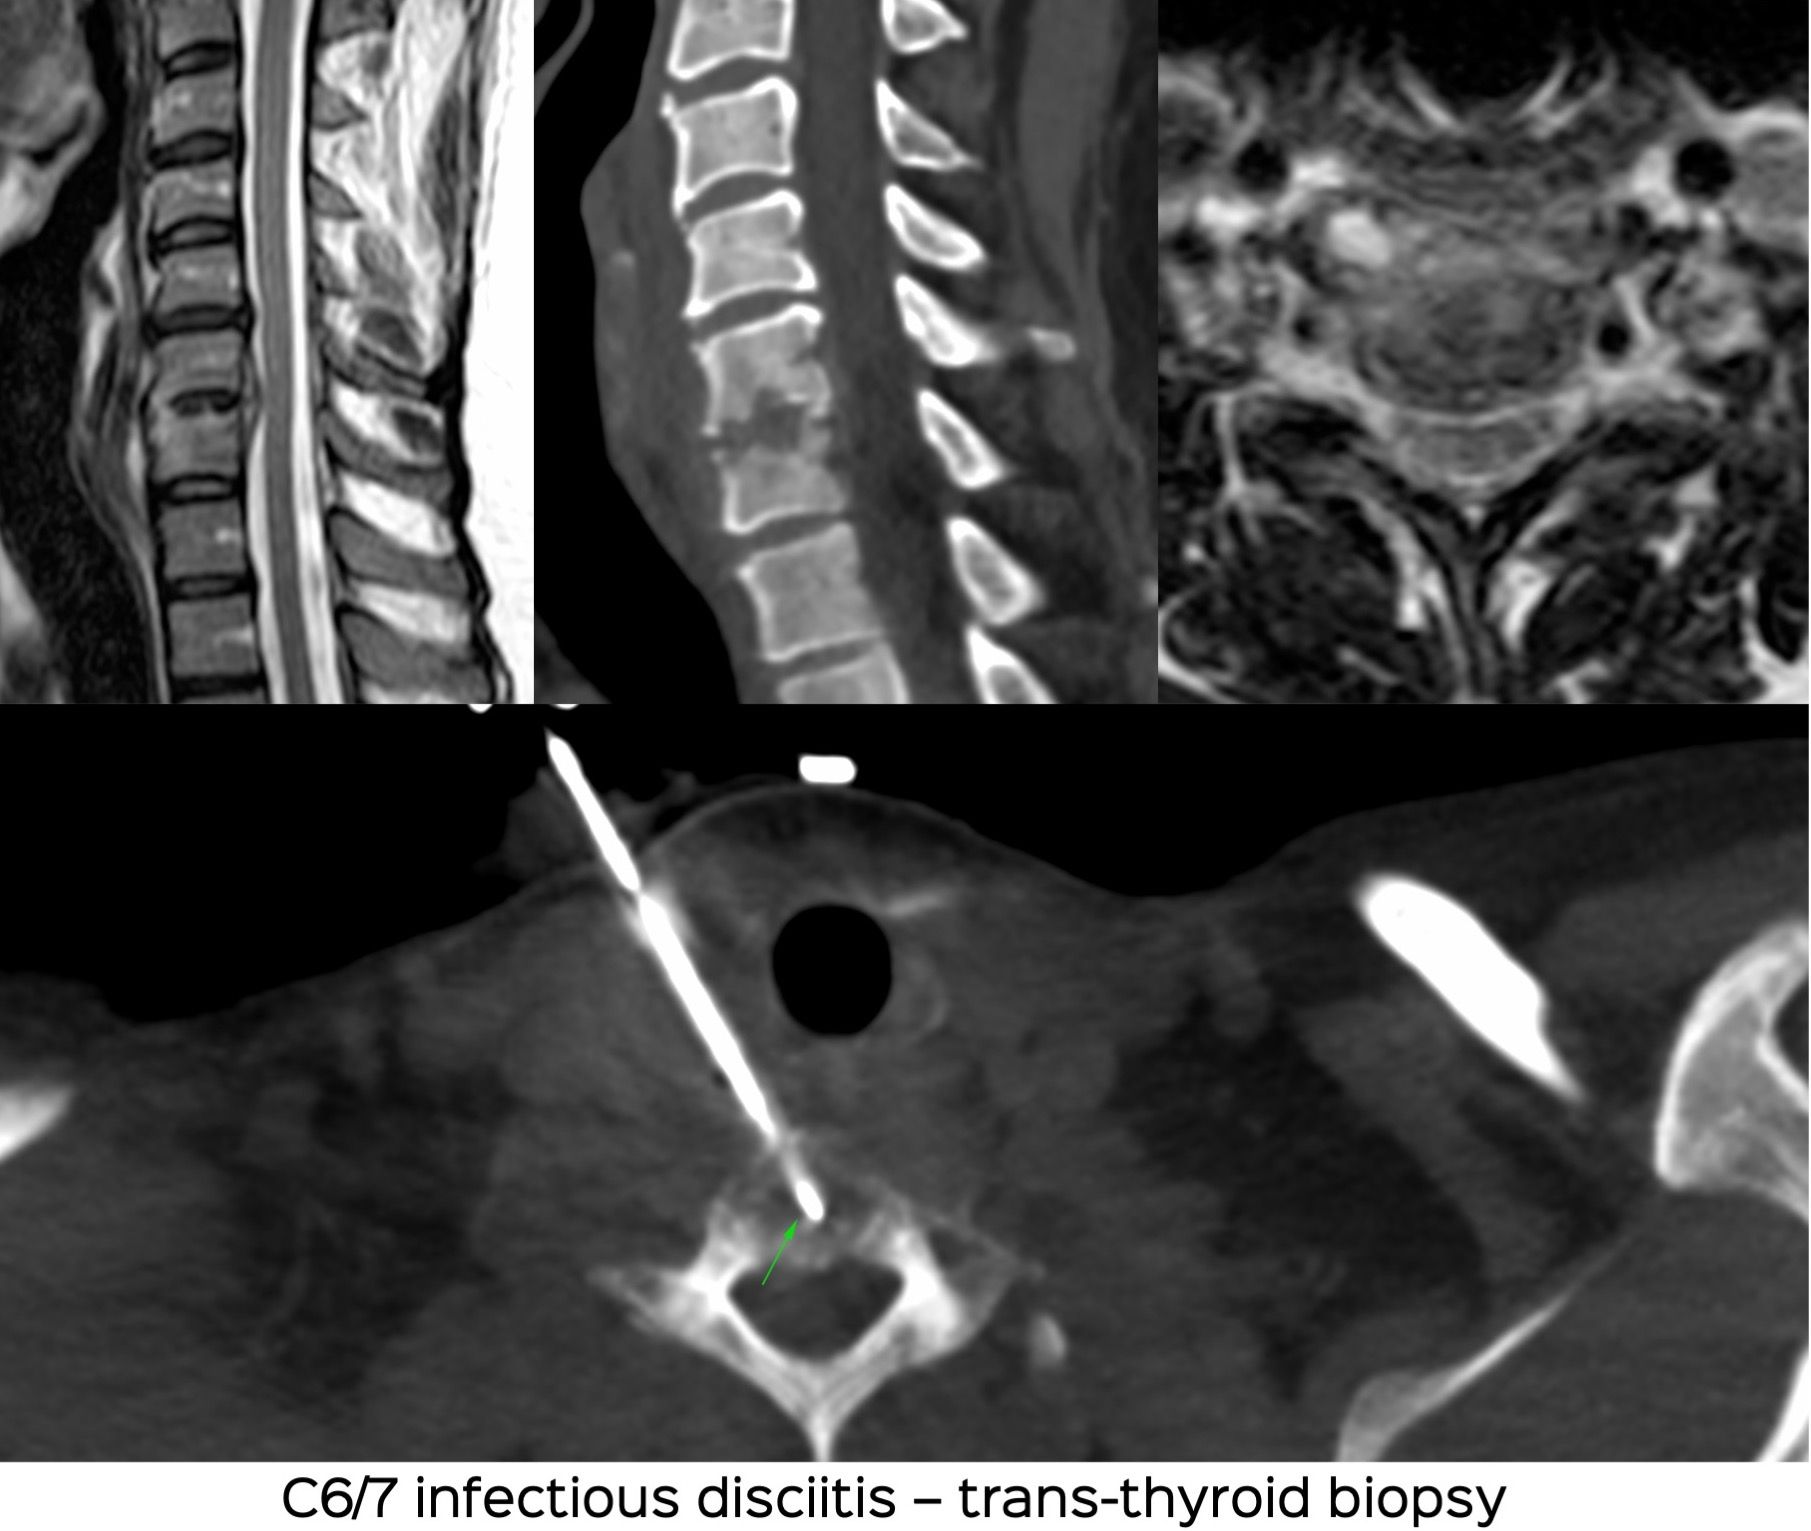

Case 26: 2nd Case - Trans-Thyroid Cervical Spine Biopsy for Infectious Disciitis

Bhavin Jankharia - 24 April 2021

Case 25: Trans-Thyroid Cervical Spine Biopsy for Infective Disciitis

Bhavin Jankharia - 21 April 2021